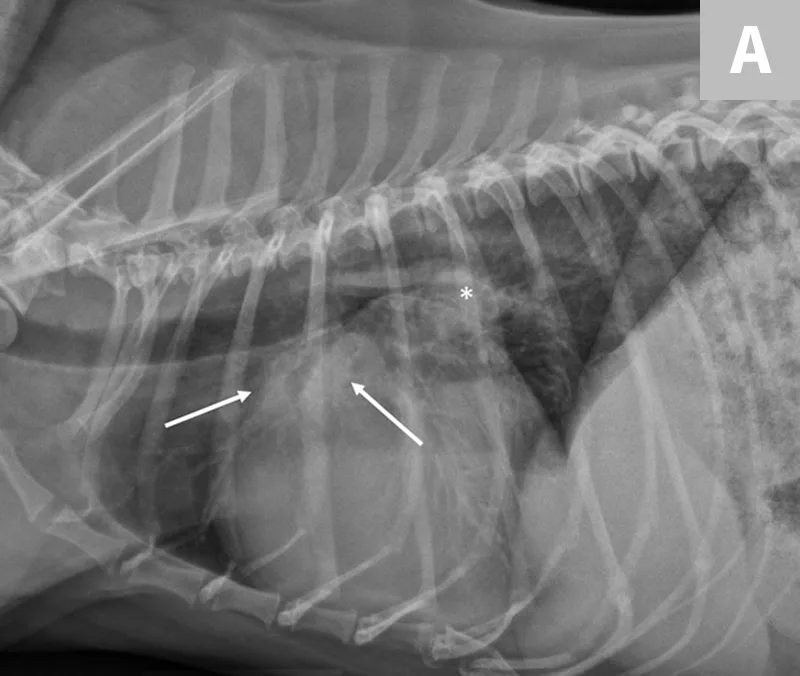

If clinical signs are not immediately life-threatening, at a minimum, a lateral thoracic radiograph should be obtained. Thoracic radiography is the gold standard for diagnosing pulmonary edema and venous congestion secondary to L-CHF.3,5 If the patient is not in distress, a 3-view study with a ventrodorsal or dorsoventral (VD/DV) view and opposite lateral thoracic views is ideal. Characteristic findings of cardiogenic pulmonary edema include increased interstitial-to-alveolar infiltrates of the perihilar and/or caudodorsal lung field in dogs.3,5 (See Figures 1A and 1B.)

FIGURE 1

(A) L-CHF in a Cavalier King Charles spaniel with mitral valve disease. Enlarged cranial lobar vessels are marked by the arrows. Enlarged left atrium is marked with an asterisk. (B) DV projection shows a caudal interstitial-to-alveolar pattern with air bronchograms (arrow). Images courtesy of University of Florida Small Animal Hospital